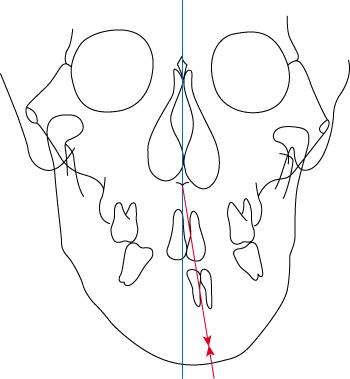

¾È¸éºñ´ëĪ

°ñ°ÝÀ̳ª Ä¡¿ÀÇ ÀüÈĹæ°ü°è°¡ Á¤»óÀÌ´õ¶óµµ Á¤¸é¿¡¼ º¸¾ÒÀ» ¶§ ÁÂ, ¿ì ºñ´ëĪÀÌ µÎµå·¯Áú °æ¿ì ¾ÇÁ¤Çü ¼ºÀåÄ¡·á¿¡ ÀÇÇØ ÇØ°áÇÒ ¼ö ÀÖ½À´Ï´Ù(±×¸²5). ±×·¯³ª °ñ°Ý¼º ºñ´ëĪÀÇ °æ¿ì ¼ºÀåÁ¶ÀýÀ» ÅëÇÑ ´ëĪÀ» ÀÌ·ç¾î¾ß Çϱ⠶§¹®¿¡ ¸¶Âù°¡Áö·Î »çÃá±â ±Þ¼ºÀå±â ÀÌÀü¿¡ Ä¡·á¸¦ ½ÃÀÛÇØ¾ß ÇÕ´Ï´Ù. ¼ºÀåÈĹݱ⳪ ¼ºÀÎÀÌ µÇ¾úÀ» ¶§ ³ªÅ¸³ª´Â ºñ´ëĪÀº ¾Ç±³Á¤¼ö¼úÀ» ÅëÇØ ÇØ°áÇØ¾ß ÇÕ´Ï´Ù.